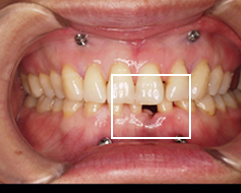

上の前歯に隙間ができてきてだんだん歯が前に飛び出してきたと来院されました。

写真(1)

治療前

下の前歯が奥に入っていて前に上に飛び出してきて上の前歯に隙間ができています。

下の歯が上の歯に隠れてしまい、ほとんど見えません。顎を動かそうにも上の歯が邪魔で顎の関節に大きな負担がかかっています。

院長の吉本の診断は以下でした

咬合不全によることが原因

マウスピース矯正、矯正インプラントを行い、全顎的な咬合改善を提案

飛び出ている歯を1本抜いて、歯茎の中にピンを入れました

矯正装置をつけ歯を動かします。インプラント矯正で飛び出た部分を下に下げます。

歯がだいたい動いてきたので、目立たない矯正装置クリアアライナー(マウスピース)を入れます。

ここまでくると矯正終了前です

治療後

下の歯も見えるようになり、楽に顎を動かせるようになりました。